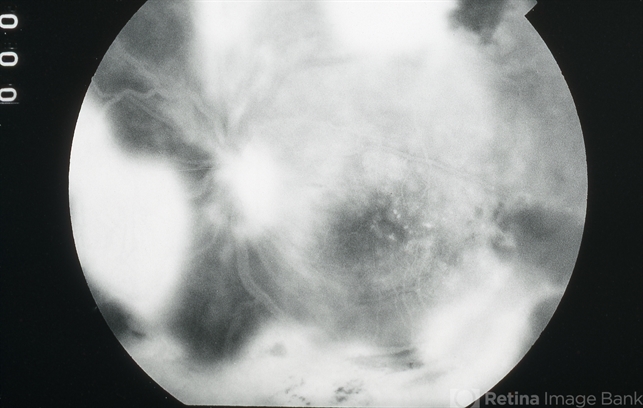

- EALES DISEASE

- Eales disease, neovascularization elsewhere (NVE), fluorescein angiogram (FA), FA late phase

- Late-phase fluorescein angiogram image of the left eye of a 23-year-old Vietnamese female with Eales Disease showing extensive dye leakage from multiple areas of NVE and from some NVD.